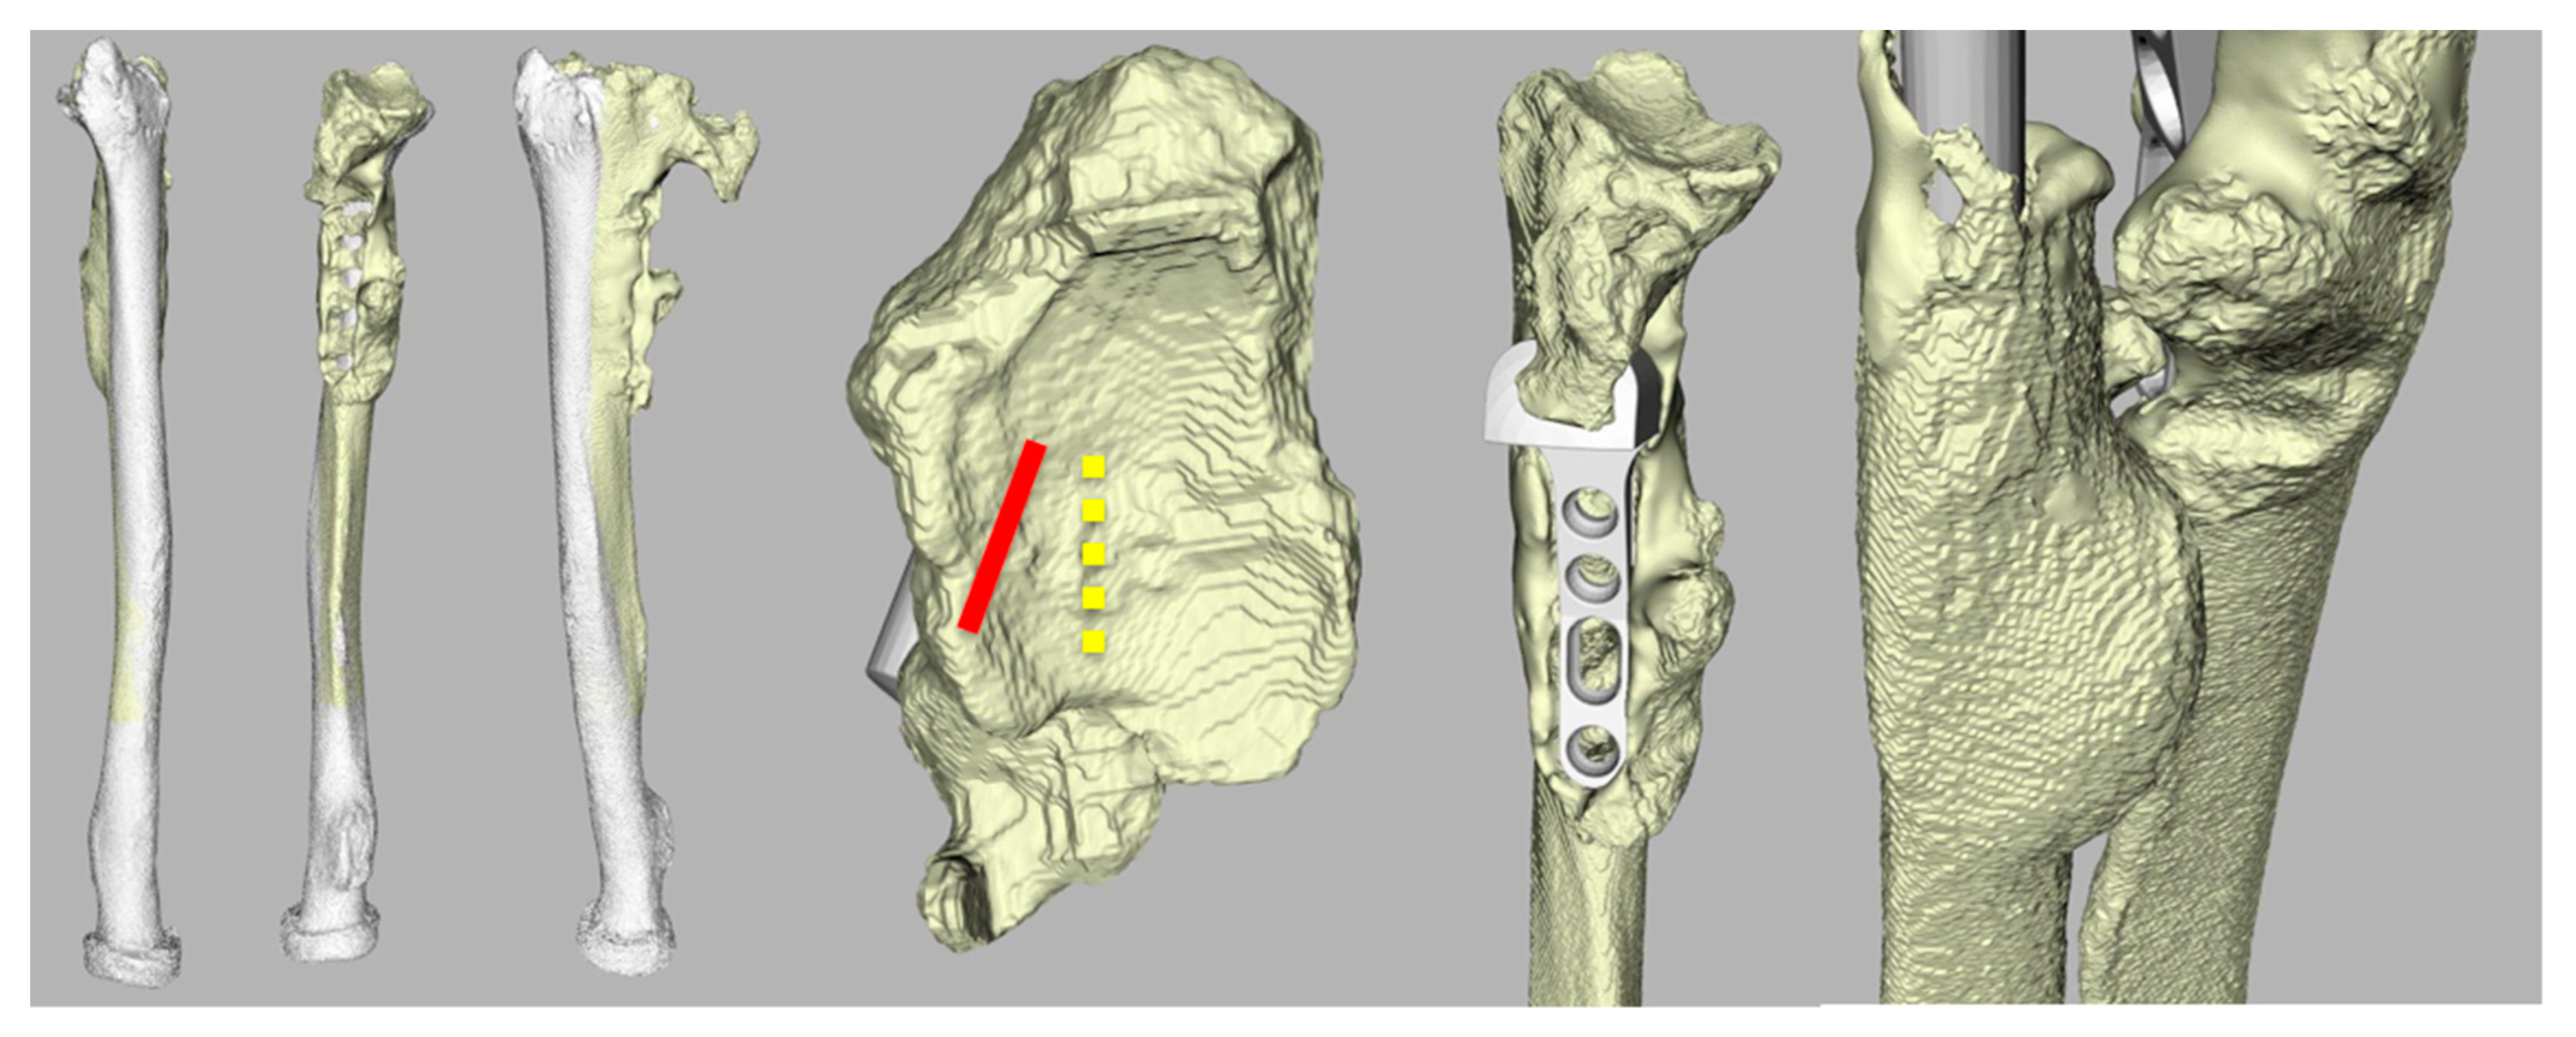

2.2. Data Collection

2.5. Radiographic Assessment

3.3. Radiological Evaluation

| Case | Radiological Evaluation | Combined Error | Translation Healthy | Translation Aptis | Δ Translation |

|---|---|---|---|---|---|

| 1 | Periprosthetic fracture; proximal screws | 11 | 1.5 | 0.5 | −1.0 |

| 2 | Lucency distal screw (37) | 6 | 2.8 | 0.6 | −2.2 |

| 3 | Heterotopic ossification (8) | 7 | 1.3 | 0.2 | −1.1 |

| 4 | No abnormalities | 5 | 2.8 | 0.5 | −2.3 |

| 5 | Heterotopic ossification (4) | 12 | 2.7 | 3.5 | 0.8 |

| 6 | - | 7 | 1.4 | 4.1 | 2.7 |

| 7 | Heterotopic ossification (5) + Lucency distal screw radius (13) | 14 | 2.1 | 0.3 | −1.9 |

| 8 | No abnormalities | 6 | 1.6 | 0.3 | −1.3 |

| 9 | Chip distal ulna (7) + Heterotopic ossification (24) | 13 | 1.8 | 0.3 | −1.5 |

| 10 | Dystrophic calcification (1.5) | 10 | 2.4 | 0.4 | −2.0 |

| 11 | Lucency distal screw (8) + heterotopic ossification (48) | 10 | 1.9 | 2.0 | 0.1 |

| 12 | Heterotopic ossification (57) | 9 | 1.7 | 0.3 | −1.4 |

| Average (SD) | 9 (3) | 2.0 (0.6) | 1.1 (1.3) | −0.9 (1.4) |